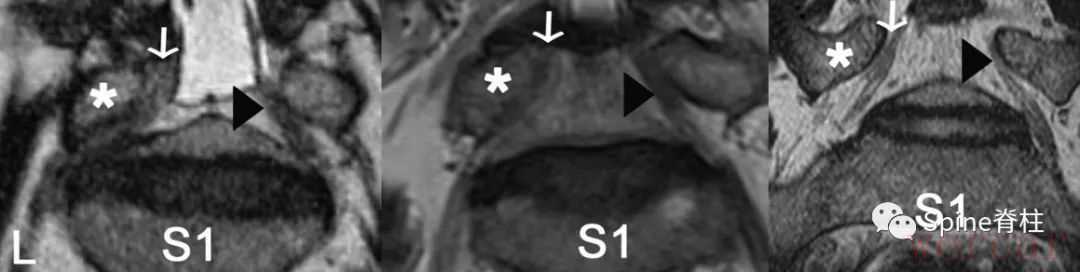

图示:L5脊神经的椎间孔角(FSN)。L5脊神经与L5下终板之间α和β角。椎间孔角应介于α和β角之间

图示:斜冠状位磁共振成像,以L5脊神经为代表。L5脊神经在L5椎弓根(*)和L5-S1椎间盘之间通过。

- 左侧图:在腰椎间孔外狭窄组中,左侧L5神经是引起症状的(白色箭头),而右侧无症状(黑色箭头)。

- 中间图:在L4-5椎管内狭窄组中,左侧L5神经为症状性侧(白色箭头),右侧为无症状性侧(黑色箭头)。

- 右侧图:在正常人组中,显示的右侧(白箭头)和左侧(黑箭头)L5脊神经。